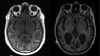

اليوم العالمي لأمراض الدماغ.. الجهاز العصبي في مرمى التحديات

يُحتفل باليوم العالمي لأمراض الدماغ سنويا في 22 يوليو، بهدف زيادة الوعي بأهمية صحة الدماغ، وتسليط الضوء على التحديات العالمية المرتبطة بالأمراض العصبية، التي تؤثر على أكثر من مليار شخص حول العالم، بحسب منظمة الصحة العالمية.